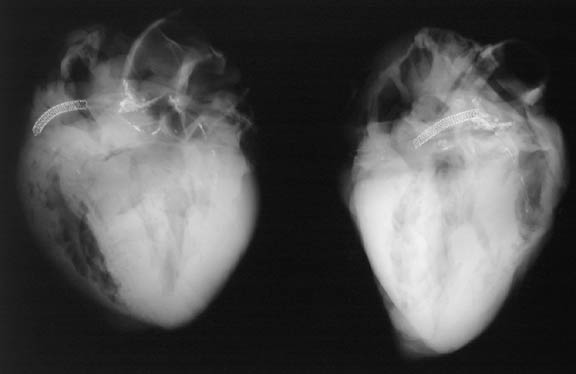

![]() | These AP and lateral radiographs postmortem reveal the presence of a right coronary artery stent that is made of wire mesh. Percutaneous translumenal coronary angioplasty (PTCA) is a common procedure performed to try and restore blood flow when a focal stenosis is present. Placement of a stent helps to keep the artery open longer following the procedure. |